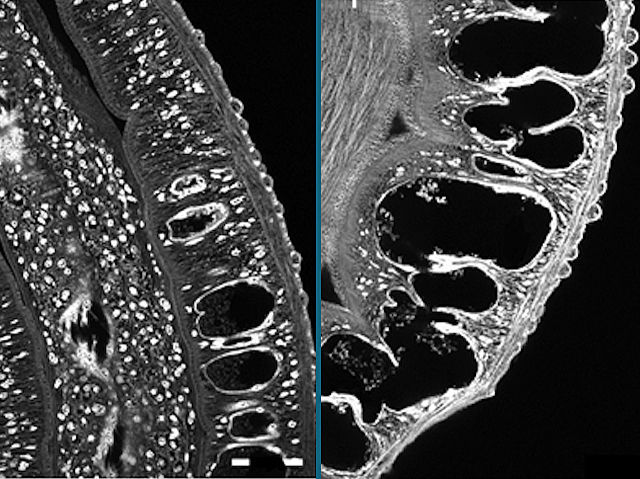

Lethal Ladybirds

A third of the world’s population is infected with parasitic worms called helminths. Schistosomiasis is one of the many diseases they cause, resulting in 200,000 deaths a year. On a mission to find new drugs to treat helminth infections, researchers turn to insects, specifically the harlequin ladybird, which produces a range of potent anti-microbials including harmonine. They tested the effects of harmonine on Schistosoma mansoni, the helminth responsible for schistosomiasis. Growing S.mansoni adults in dishes with harmonine resulted in damage to several tissues needed for their survival, including outer protective layers, reproductive organs, and the gut. The guts of harmonine-treated helminths (pictured, right) were distended compared to untreated helminths (left), as revealed by confocal microscopy. Increasing the dose of harmonine resulted in further damage and the eventual death of S.mansoni adults. These results provide new avenues for research into novel compounds to combat the diseases caused by helminths.